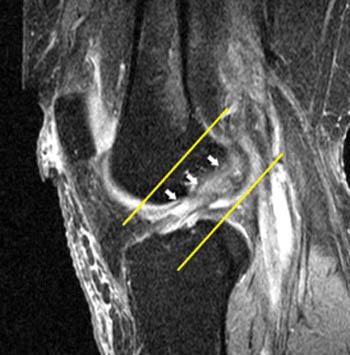

The anterior cruciate ligament is one of four ligaments in the knee which sits deep inside the joint. 25.07.2019 · the anterior cruciate ligament, or acl, is a part of the knee that is prone to injury. It's located diagonally in the front of your knees, connecting the femur to the tibia and providing stability to the knees when you rotate your legs. It is also the most injured ligament while playing sports. Because it's not something that occurs gradually, the person will … 22.07.2021 · the acl is a tough band of tissue joining the thigh bone to the shin bone at the knee joint. When the knee is extended, the acl has a mean length of 32 mm and a width … It runs diagonally through the inside of the knee and gives the knee joint stability. The anterior cruciate ligament (acl) is a band of dense connective tissue which courses from the femur to the tibia. The acl is a key structure in the knee joint, as it resists anterior tibial translation and rotational loads. An acl injury is a partial or complete tear, a stretched ligament, or a detachment of the ligament from your bone. Acl stands for anterior cruciate ligament. When a person suffers from an acl tear, he or she will immediately experience knee pain.

The acl is a key structure in the knee joint, as it resists anterior tibial translation and rotational loads.

25.07.2019 · the anterior cruciate ligament, or acl, is a part of the knee that is prone to injury. It's located diagonally in the front of your knees, connecting the femur to the tibia and providing stability to the knees when you rotate your legs. Anterior means situated at the front, cruciate means shaped like a cross and a ligament is a band of tissue connecting bones. An acl injury is a partial or complete tear, a stretched ligament, or a detachment of the ligament from your bone. When the knee is extended, the acl has a mean length of 32 mm and a width …